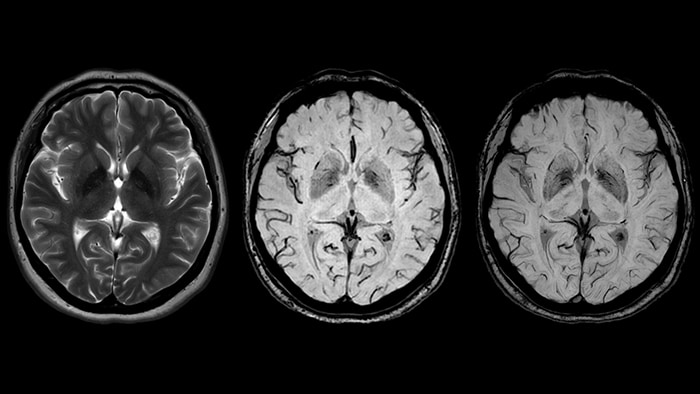

Иллюстрации и пояснения: гиподенсивный очаг на КТ головного мозга